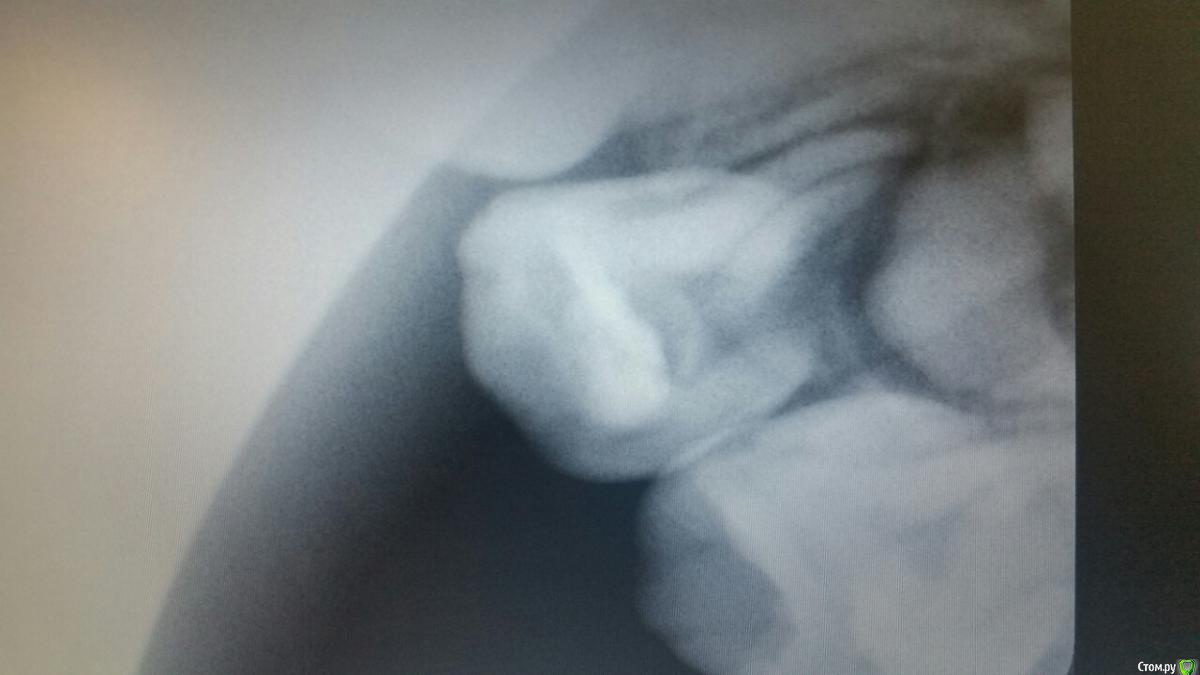

Ребенку скоро 4 года. Чуть более года назад был пролечен поверхностный кариес верхней четверки. В настоящий момент над пролеченным зубом возник небольшой белый "прыщик". Сходили к доктору, удалили старую пломбу, пульпа твердая, живая. Пульпу вскрывать не стали. Сделали снимок. Получили рекомендацию смотреть состояние в динамике. Ребенок ни на что не жалуется, зуб не шатается, при накусывании этим зубом твердых предметов боли не ощущает. Что это периодонтит? Ждать или принимать срочные меры? Спасибо!